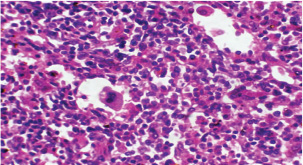

Histopathological examination of rabbits infected with T. annulata (G2) demonstrated progressive pathological alterations in various organs, in contrast to the control group (G1), which exhibited no abnormalities. At 14 days of post-infection, the lungs exhibited moderate alveolar thickening, hyperemia, and the presence of developed schizonts, indicating early tissue involvement (Fig. 4). The liver showed multiple necrotic areas, extensive venous congestion, and parasitized red blood cells, suggesting severe hepatic distress (Fig. 5). The spleen exhibited scattered macrophages containing microschizonts and hemosiderin-laden macrophages, reflecting both immune activation and erythrocyte breakdown (Fig. 6). The kidneys were affected by tubular infiltration with parasitized mononuclear cells (MNCs) (Fig. 7), whereas the mesenteric lymph nodes showed marked architectural disruption and merozoite aggregation (Fig. 8), suggesting significant immune system involvement.

Fig. 6. A histopathological section of the spleen of (G2) at 14 days postinfection shows the scattered presence of macrophages containing micro-schizont (black arrow) and hemosiderin laden macrophages (red arrow) (H&E stain X 40).

Fig. 7. A histopathological section of kidney of (G2) at 14 days postinfection showing tubular infiltration with parasitized mononuclear cells (black arrow) (H&E stain X 40).